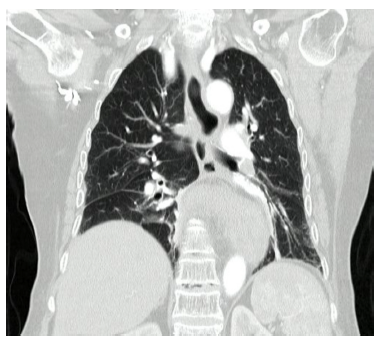

Posteriormente se realizó tomografía de abdomen y tórax con contraste, donde se evidencia hernia de la unión gastroesofágica, fondo y unión antropilórica del estómago hacia el tórax, además de una rotación del estómago en su eje largo, que configura vólvulo gástrico organoaxial (Figura 2).

Figura 2 Escanografía de tórax: se observa hernia de la unión gastroesofágica, fondo y unión antropilórica del estómago hacia el tórax, además de rotación del estómago en su eje largo.